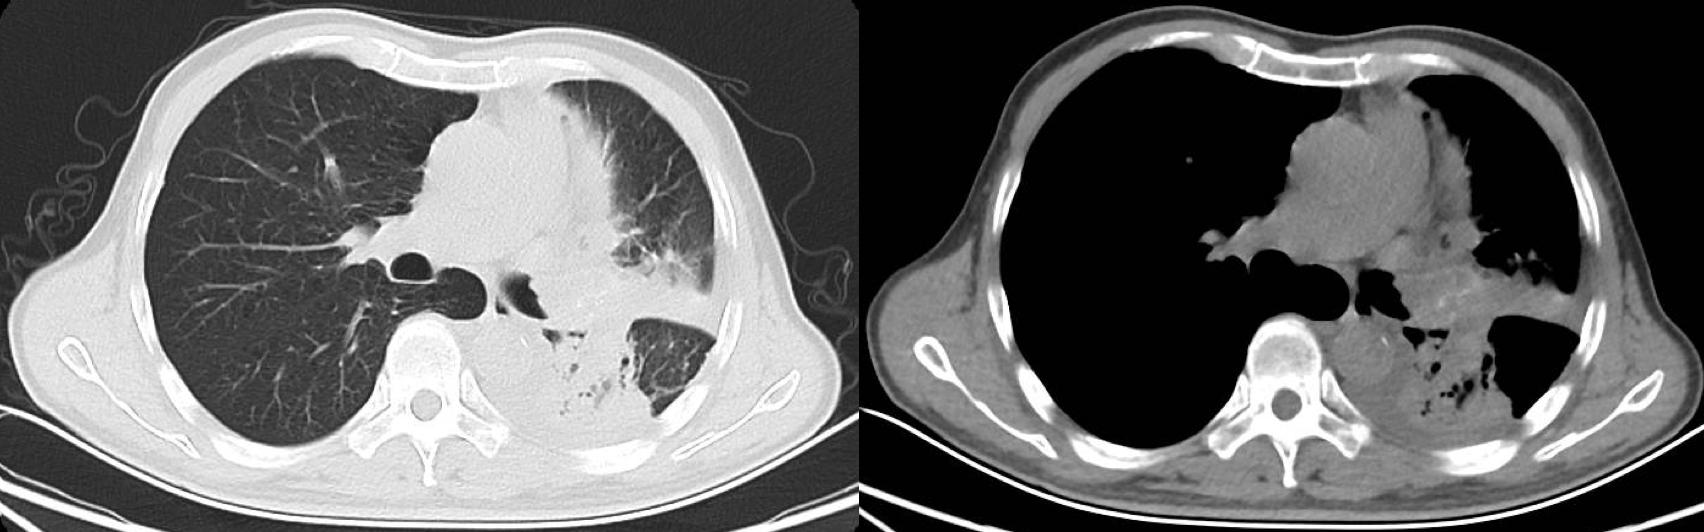

但是,来北京半个多月了,肿瘤已经有所进展,把左主支气管堵死了。老刘出现了阻塞性肺炎,高烧39度,左侧的胸廓有所塌陷,走10步路都喘得厉害,不尽快治疗的话,老刘危在旦夕。

左肺门肿块堵塞支气管,导致阻塞性肺炎